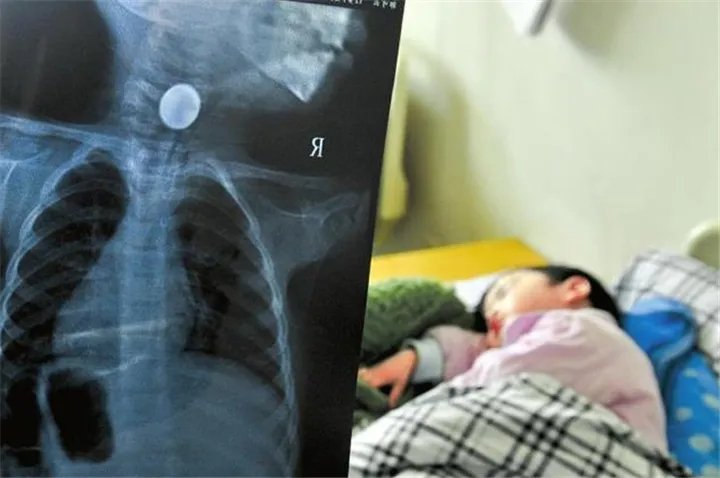

不久前,张女士的三岁女儿在赣县的燕燕在玩耍时不小心吞下了一毛钱,被卡在食道的入口。

由于交通拥堵,到医院花费了一个多小时。在这段时间里,孩子处于半昏昏欲睡的状态,使张女士感到恐惧,“我哭了好几次。”只是在拍完胶卷后,硬币仍然卡在食道中,这是非常危险的。

那天下午,刚到医院的燕燕被送进手术室。当她在手术前就位时,她发现硬币已经进入她的胃中,并且孩子的食道受到了部分破坏。

小女孩见到燕岩,已经忘记了以前的痛苦,与母亲保持亲密关系。医生介绍说,燕岩的病情确实更加危险。尽管她卡在食道中,但很容易引起窒息,因为它现在已经进入胃中,可以通过排便使用药物将其排出。护士长还警告孩子现在已经处于危险之中,但是由于成人起初强行将一枚硬币放在喉咙里,它伤害了孩子的食道,目前最好吃流质食品,吃完后漱口,以免发炎。